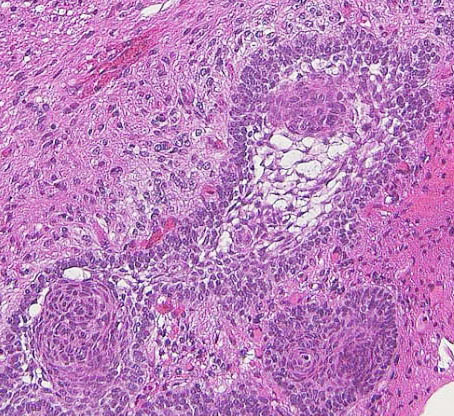

成人の第3脳室内部に局在する頭蓋咽頭腫です。経脳梁法で両側のモンロー孔から全摘出しました。下垂体組織は残っています。これは乳頭状頭蓋咽頭腫と呼ばれるもので,成人にしか発生しません,のう胞がなく石灰化もないのが大きな特徴です。境界が明瞭で柔らかく摘出が簡単なタイプとして知られています。この患者さんも術後に下垂体機能不全も視床下部障害も生じませんでした。

Monomorphous mass of well-differenciated squamous epithelium lacking surface maturation and wet keratin.

乳頭状頭蓋咽頭腫 papillary craniopharyngioma

- 成人のみに発生する良性の頭蓋咽頭腫です

- adamantinomatous typeとは異なった腫瘍ではないかと思えるくらい違います

- 平均年齢は40-55歳くらいで中年以降です

- 第3脳室内部に発生します

- ですからトルコ鞍内腫瘍でも鞍上部腫瘍でもありません

- 画像診断では,第3脳室内に,境界明瞭な,ガドリニウムで全体が増強される,石灰化ものう胞も無い腫瘍として診断されます

- 石灰化がありません

- 固形腫瘍であり,のう胞形成はとてもまれです

- ですからコレステロールを含む機械油のような内容液がありません

- adamantinomatous typeと比較して脳組織浸潤が少ないです

- 病理は,fibrovascular coreを中心として,ケラチンを含まない分化度の高い”非角化型”扁平上皮の単純な増殖です